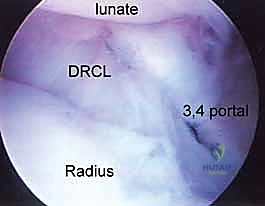

- Function: Indicated for evaluating the dorsal radiocarpal ligament (DRCL) and the palmar portion of the scapholunate interosseous ligament (SLIL). It provides a clear view of dorsal rim fragments for arthroscopic reduction of intra-articular distal radius fractures.

- Function: Indicated for visualizing and débriding palmar tears of the lunotriquetral ligament (LTIL). It aids in the repair or débridement of dorsally located TFCC tears, especially when triangulation from dorsal portals is difficult. It also assesses the dorsal radioulnar ligament, the ECU subsheath, and the radial TFCC attachment.